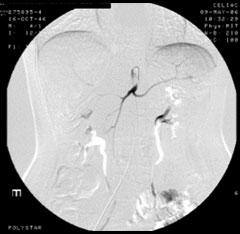

症例9

54歳 男性

両下肢間歇性跛行(100m)

平成17年より間歇性跛行(100m)出現。

Pletaalにて加療するも症状の改善なし

平成18年5月当院紹介受診。

【既往歴】

52歳 DM・CRF→HD中

54歳 狭心症→PCI

高血圧(+) 喫煙歴(50本×30年)

ABI:右0.7 左0.9 (高度石灰化)

【治療計画】

当日考える

症例9 MRA / CT